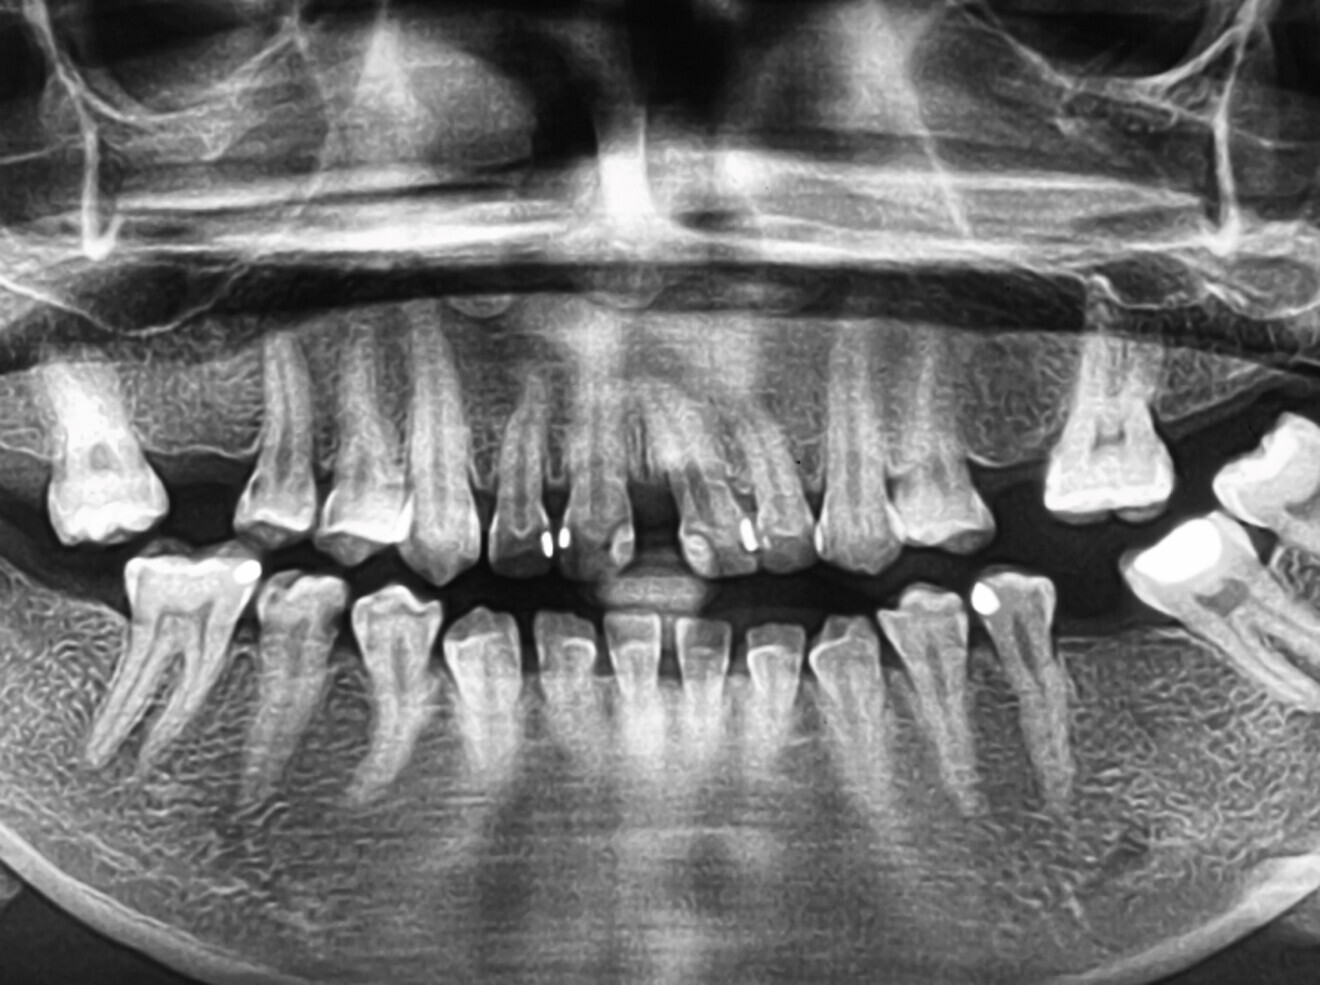

Panoramic radiograph analysis:

Missing 17, 26, 38, 36, 46 and 47.

Retained root 16, 45.

Poor prognosis 26.

Increased vertical bone loss especially 11,21 (only ~30% left)

Missing 18, 16, 25,26, 28, 36, 47 and 48.

20-30% vertical bone loss upper anterior region.